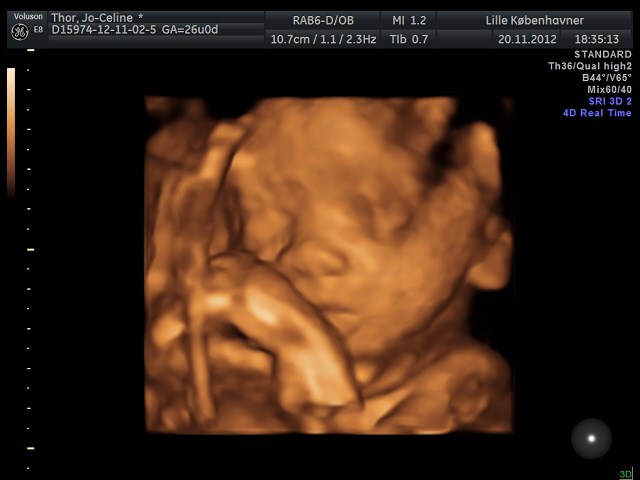

Søger man på Google kommer der kun 3D-billeder.

Så jeg vil høre om nogen herinde har et billede eller to fra uge 28 de vil vise? Og hvor lang var jeres baby, og fik I vægt at vide?